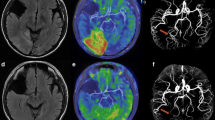

The four clinical images diagnosed MELAS are shown in Fig. 5. In the positive case diagnosed with MELAS, based on the decision boundaries obtained from the LDA of the rCBF values, there was a clear increase in blood flow from the right cuneus to the temporal lobe (Fig. 5a). In the positive case diagnosed with MELAS from the LDA of nSI, there was a clear T2 prolongation area in the right occipital lobe and from the left cuneus to the left temporal lobe, and increased blood flow on ASL images consistent with the same area (Fig. 5b). In the case that was not distinguished as MELAS using the decision boundaries obtained from the rCBF values and nSI, the right cuneus to the right occipital lobe was the site of the lesion; however, there was no obvious increase in blood flow and area of T2 prolongation (Fig. 5c). In the case of MELAS diagnosed on the border of the decision boundary obtained from the LDA of nSI, the right cuneus to the right temporal lobe was the site of the lesion, but there was no obvious T2 prolongation area, while ASL images showed an obvious increase in blood flow in the same area (Fig. 5d). The AUCs for the ASL and FLAIR images were 0.889 and 0.804, respectively, as estimated from the ROC curves using the rCBF values and nSI (Fig. 6). There was no significant difference between the two AUC values (p = 0.173).

In this study, we examined the clinical utility of FLAIR imaging for the diagnosis of MELAS with recurrent SLEs compared to ASL imaging. The results showed that the rCBF values obtained from ASL images and the nSI obtained from FLAIR images were equivalent to their diagnostic performance in MELAS cases. We calculated Spearman’s rank correlation coefficient using the rCBF values and found no correlation between the normal and MELAS groups. We considered that the degree of increased blood flow in recurrent SLEs varied by case. However, as shown in Fig. 3, the overall rCBF values were higher in the MELAS cases than in the normal cases, especially in the cuneus. Therefore, only the degree of increased blood flow can easily indicate an abnormality of the brain; this is consistent with findings of previous reports [7, 8]. In contrast to the rCBF values, there was a strong positive correlation in the nSI results. The high correlation of the nSI obtained from FLAIR images is due to the smaller signal intensity in MELAS cases and normalization of the signal intensity by dividing it by the signal intensity of the brainstem. We considered that the correlation coefficient of nSI was also higher because normalization allowed the variation in signal values to be compared between cases. Based on the decision boundaries obtained from LDA, both the sensitivity and specificity for diagnosing MELAS using the rCBF value were higher than those of the nSI; however, there were few differences. Regarding sensitivity, in the positive cases diagnosed with MELAS on the border of the decision boundary obtained from the LDA of nSI, one MELAS-positive case could be distinguished by the ASL image, which was the cause for the slight difference. We considered that the difference in specificity was due to the larger rCBF values of cuneus in MELAS cases than in normal cases, and the smaller signal intensity in MELAS cases and the smaller difference between MELAS and normal cases. Care must be taken in cases of MELAS that cannot be distinguished using either rCBF values or nSI. In this study, MRI examination of recurrent SLEs was performed; however, there were no abnormalities on the ASL or FLAIR images (Fig. 5c). Li et al. reported that persistent cellular injury due to impaired adenosine triphosphate production may give rise to excessive loss of neurons, resulting in decreased rCBF in the affected brain regions during the chronic phase of SLEs [7]. Therefore, our method is not appropriate for these cases, and we need to perform a comprehensive diagnosis in conjunction with physical findings and other examination results. We calculated AUC values from ROC analysis using rCBF values and the nSI, and recognized that ASL images have better diagnostic performance than FLAIR images.